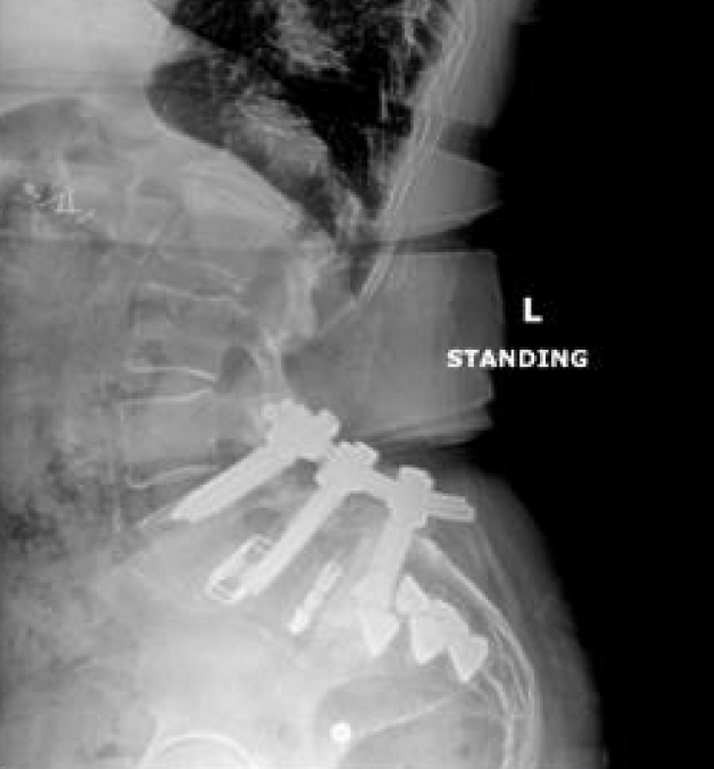

- High lumbar lordosis (77°) & pelvic incidence (86°)

- L4-5 & L5-S1 MIS transforaminal interbody fusion, November 2017

- Revision open L4-S1 fusion for pseudoarthrosis and hardware loosening, March 2019

- Bilateral SI joint fusion using the iFuse 3D™ Implant System, August 2020

Post-op:1

- Post-op resolution of bilateral SI joint pain.

- CT of lumbar spine at +2 years post-op shows confirmation of the SI joint fusion.

Inline dennis 04